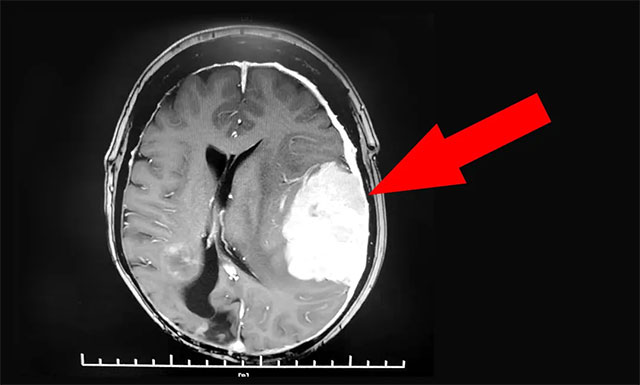

▲ 患者左侧颞顶叶巨大占位

经外院检查,发现患者左侧颞顶叶占位予以保守治疗。半年后患者病情进一步加重,复查发现占位区域水肿较前进展,中线发生明显偏移,脑组织受压程度严重,随时可能出现危及生命的脑疝,病情十分危重。

沈建康教授团队首先为患者进一步完善检查,头颅MRI增强检查显示,患者左侧颞顶叶部位的肿瘤约为6.3cm×4.4cm×6.7cm,体积巨大。经行DSA检查发现,肿瘤包裹缠绕多根重要的动脉血管,血供非常丰富。尽管切除难度高,手术风险大,但综合分析考虑肿瘤为脑膜瘤,系良性肿瘤,手术成功可以治疗好。